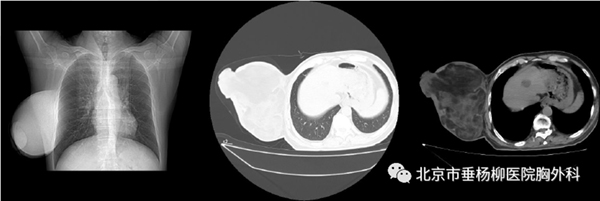

患者,男性,68岁,主因“发现右前胸壁肿物12年,破溃半月”来诊。患者12年前无意间发现右前胸壁肿物,鹌鹑蛋大小,无任何症状,因此一直未诊治。半月前发现胸壁肿物局部出现破溃,并伴有感染,同时有脓性分泌物,可闻及恶臭,多家医院换药后感染未见好转,并且逐渐加重。最终就诊于北京市垂杨柳医院胸外科,胸外科副主任医师崔健详细询问病史并且仔细查体后,表示可手术切除,并立即收住入院。入院以后完善胸部CT检查,提示右前胸壁肿物,最大直径约19cm,脂肪密度为主,与周围组织界限清晰。查体右侧胸壁巨大软组织肿物,表面局部破溃、化脓,质韧,大小19*17*13cm,活动度大。完善相关术前检查后,2023年8月4日全麻下行右侧胸壁软组织肿瘤切除术,为尽量保留正常皮肤,术中沿肿物基底部上缘约2cm切开皮肤,术中见肿物包膜完整,仔细游离并最终将肿物完全切除。创面皮肤可无张力对合,避免了术中皮瓣移植,缝合皮下组织,间断缝合皮肤。手术后称量肿瘤重2690g。术后患者恢复顺利,伤口愈合良好,术后4天顺利出院。

胸部CT可见右侧胸壁巨大肿物,直径约19cm